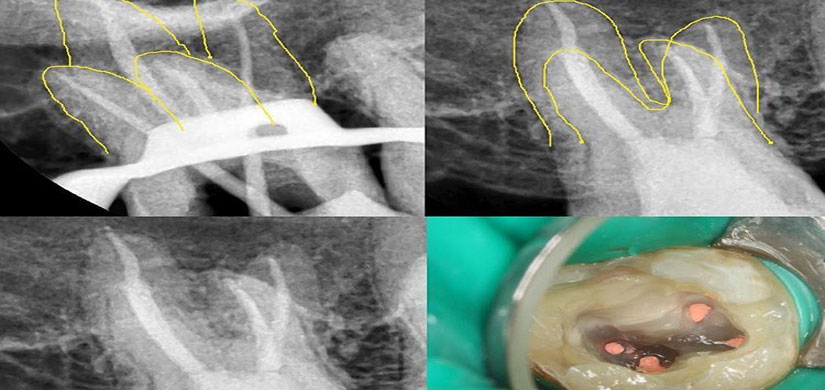

La terapia endodontica viene utilizzata quando una lesione, come una carie o un trauma, causa un danno irreversibile alla polpa dentaria, arrivando fino alla sua necrosi. Viene anche applicata in caso di precedenti trattamenti endodontici senza successo o in presenza di lesioni periapicali come cisti, granulomi o ascessi.